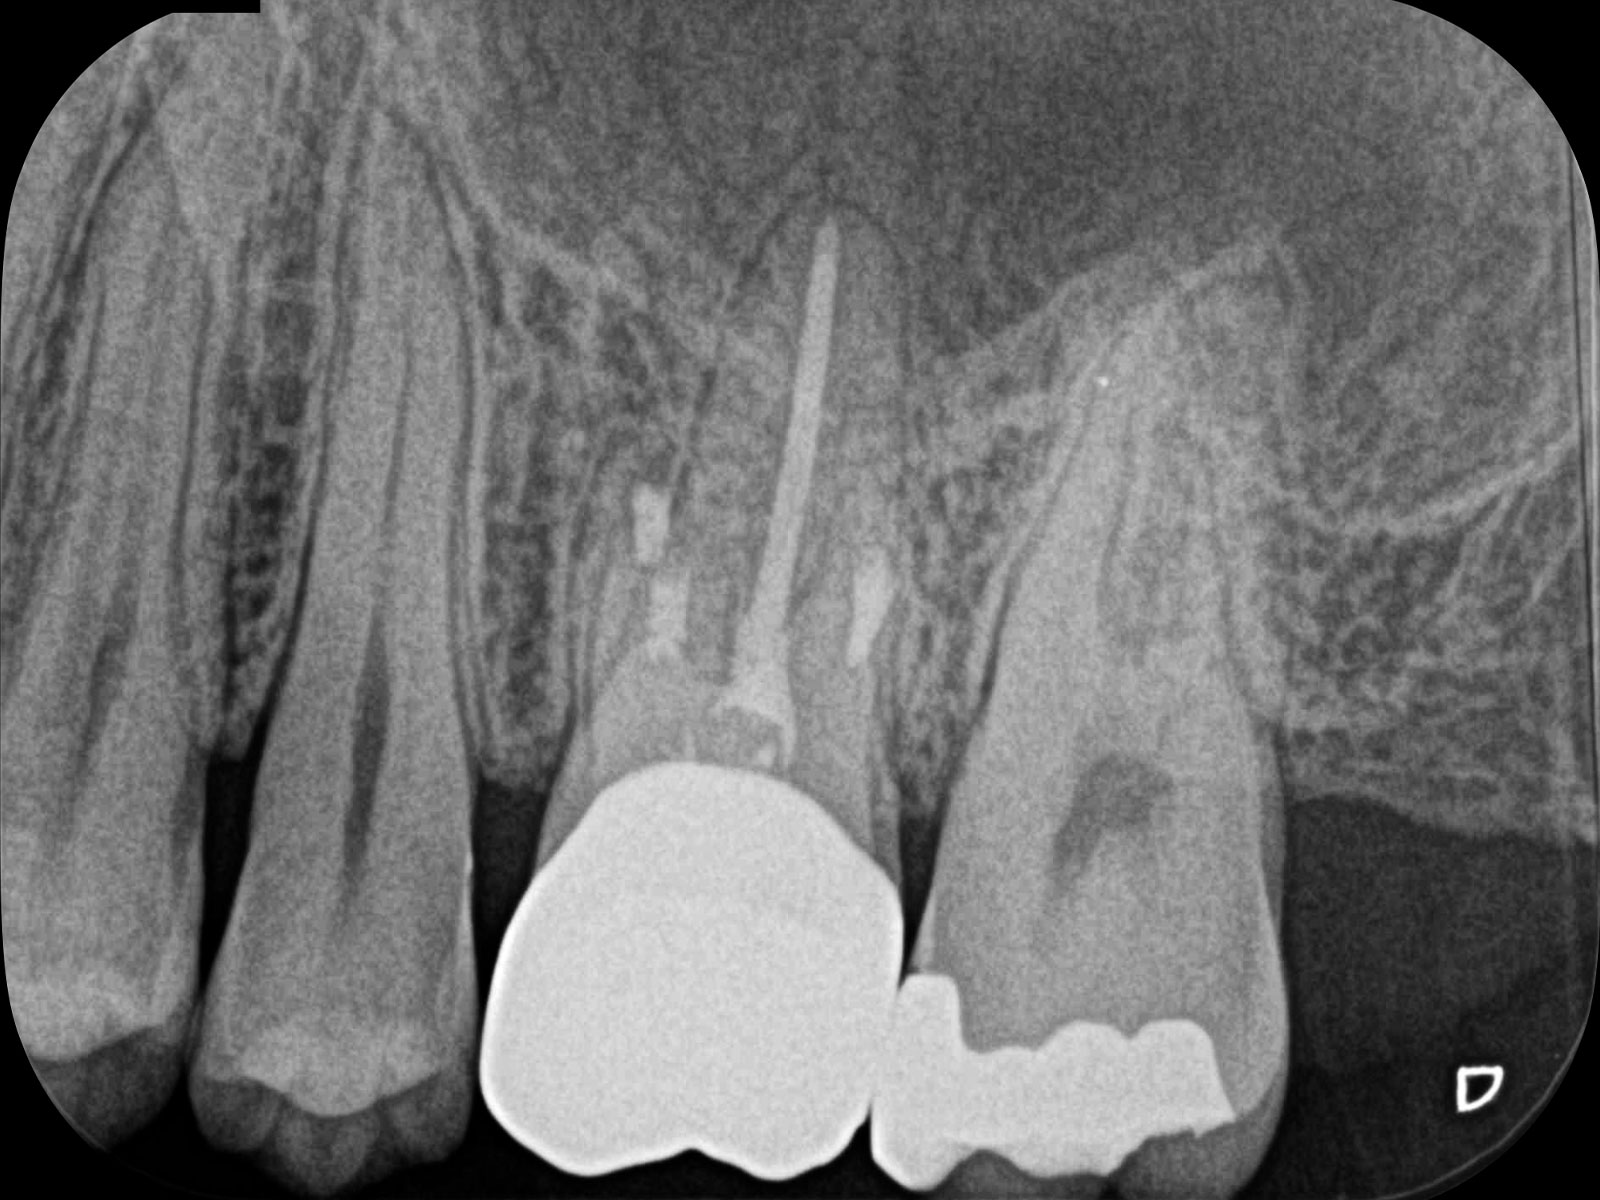

主訴: 噛むと痛い、左で食べれない。他の病院で神経が見つからない。根の先に病気がある。

通常だと手立てがなく、抜歯しかない歯も外科(根尖切除術)で治すことができます。